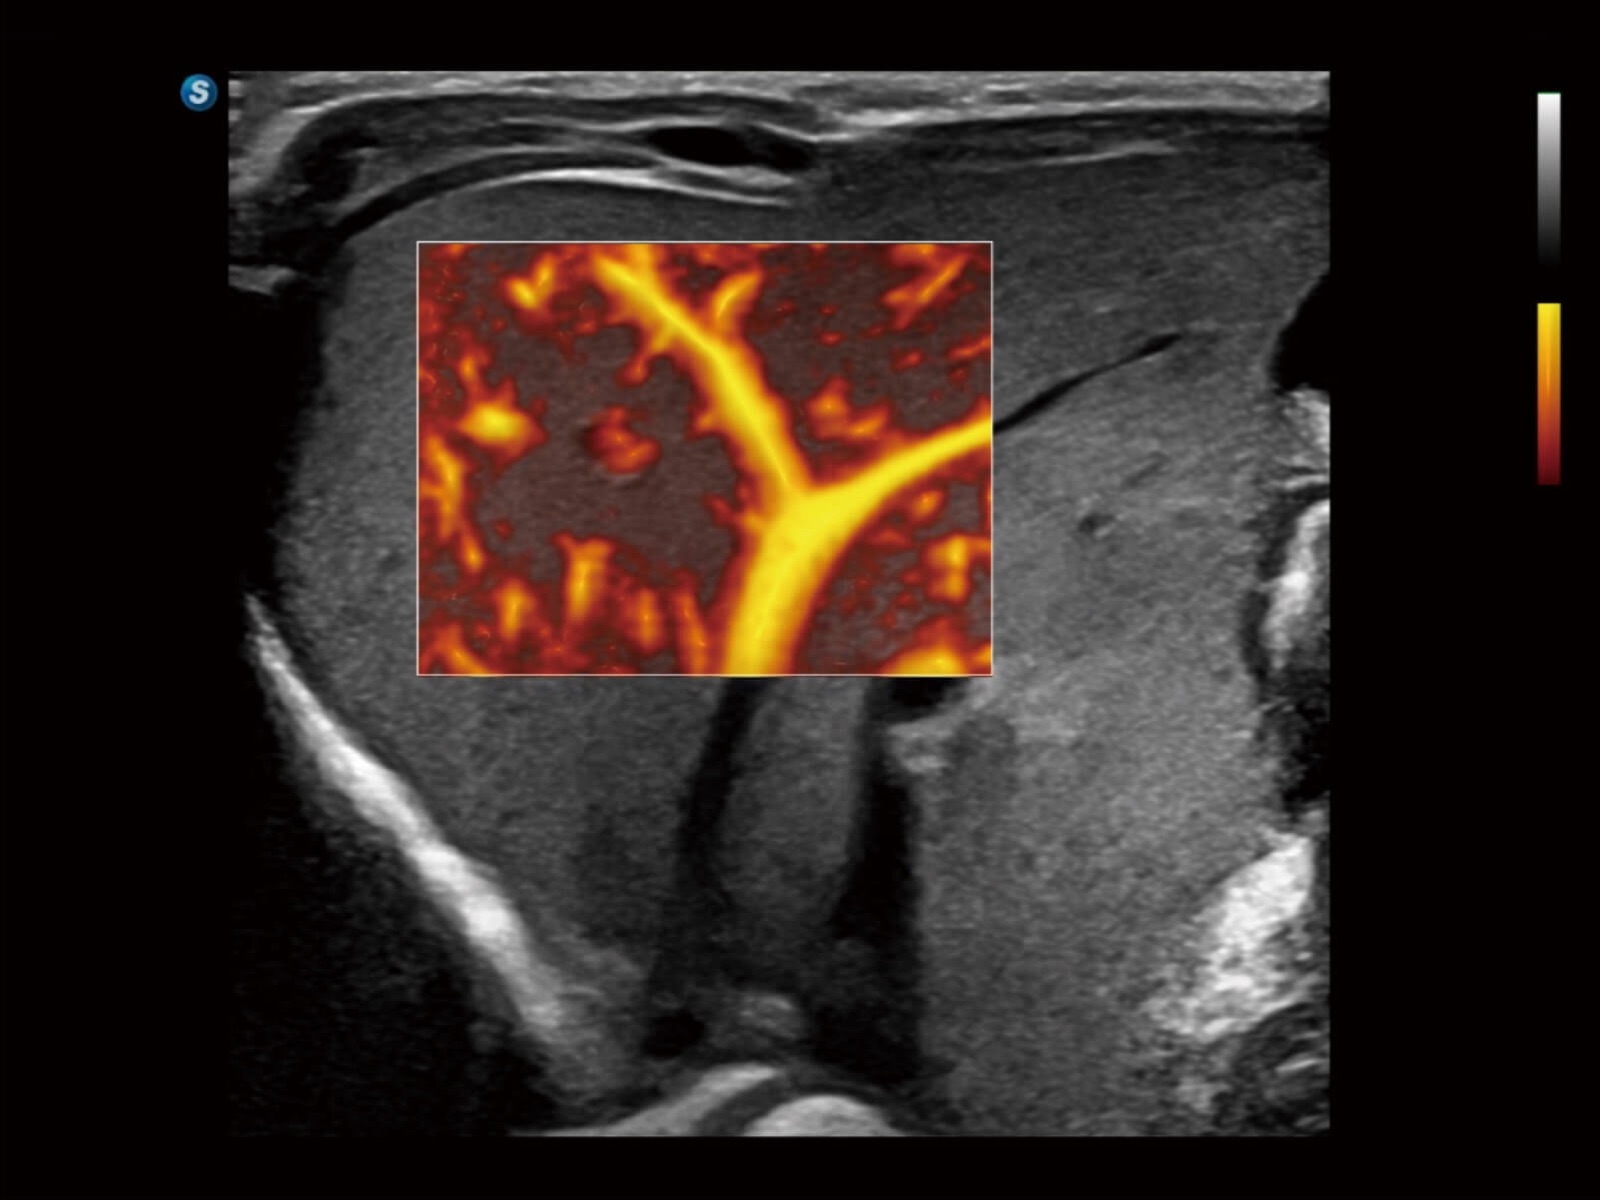

Bright Flow立体血流成像

通过光照模型,使二维血流显示出立体的效果,增加血流的敏感性、成束性,减少外溢。可以和其他不同的血流技术联合使用,轻松应对微小血管,增强血流的立体效果,提升视觉敏感性。